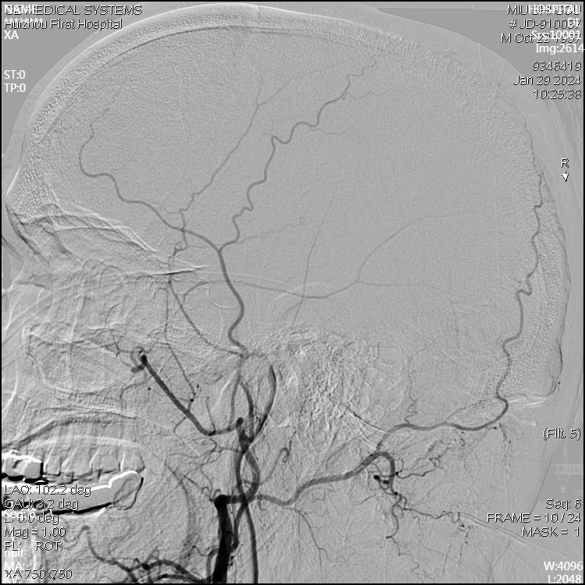

急诊DSA未见畸形血管。

右侧椎动脉正位片

右侧椎动脉侧位片